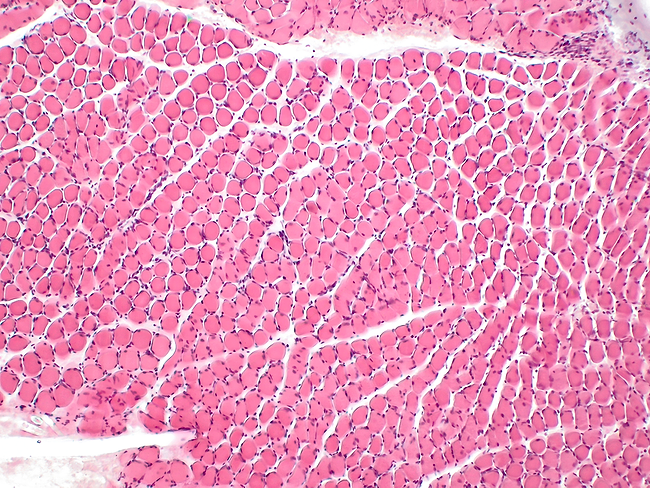

3d illustration of human body muscle tissue anatomy

Irodanoprost improves muscle function and histology in experimental DMD

Prostaglandins induce the regeneration of muscle in rodents and humans through the prostaglandin E2 receptor EP4 subtype receptor, but this therapeutic pathway's potential is limited due to systemic tolerability. Researchers from Mesentech Inc. recently presented new results on their prostaglandin E2 receptor EP4 subtype receptor agonist irodanoprost trying to address this limitation issue.